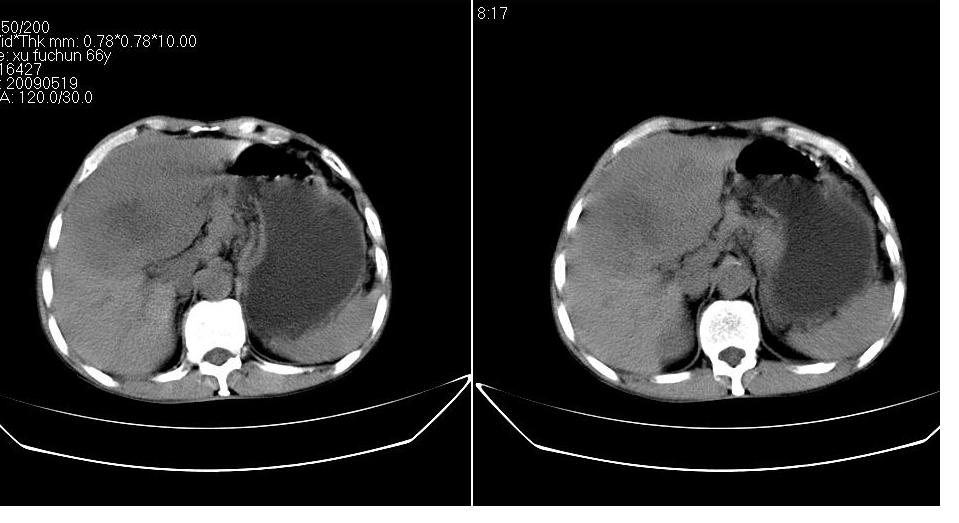

标题: CT20033:上腹部CT平扫

男 66岁,腹疼,b超提示考虑肝癌。

考虑巨块型型肝癌坏死、出血。建议增强。

考虑巨块型肝癌可能性大;建议行进一步检查。

考虑肝左叶巨块型肝癌可能性大;建议行增强ct扫描。